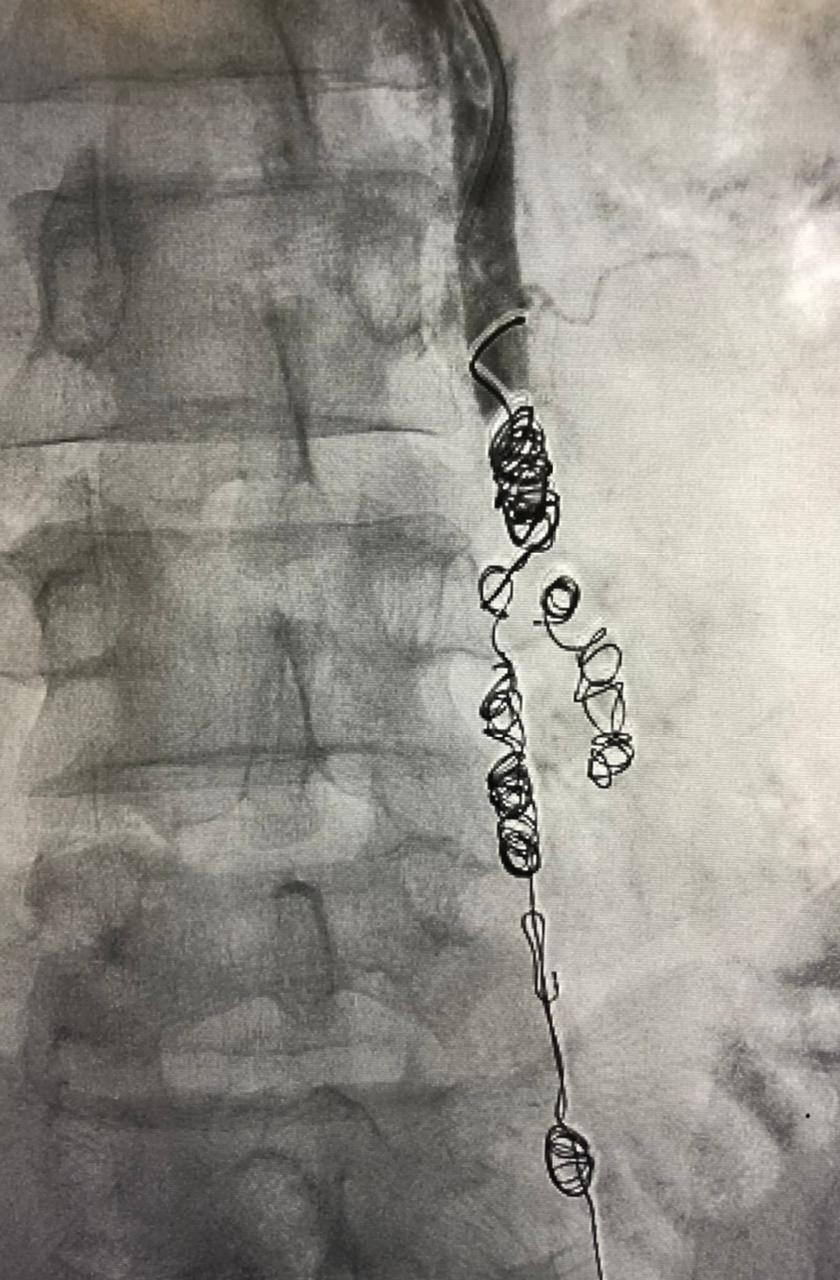

وأوضح رئيس الفريق استشاري الأشعة التداخلية الدكتور محمد شراحيلي أنه تم تحديد واستكشاف جميع الأوردة المسببة لارتجاع الدوالي وتم علاجها باستخدام اللفائف المعدنية الدقيقة وحقن المادة المتصلبة

وأبان أن تقنيات الأشعة التداخلية باستخدام القسطرة تحت استرشاد الأشعة الصوتية و الفلورية من أحدث الطرق العلاجية لدوالي الحوض ،حيث يتوفر العديد من تقنيات العلاج ومنها إغلاق الوريد المتسبب في الدوالي باستخدام اللفائف المعدنية الدقيقة أو من خلال حقن مادة صمغية أو تصلبية ويتم الوصول لتلك الأوردة من خلال فتحة دقيقة بالجلد لذراع المريض لا تتجاوز الـ 2 ملم، لا تترك علامات جراحية على الجلد